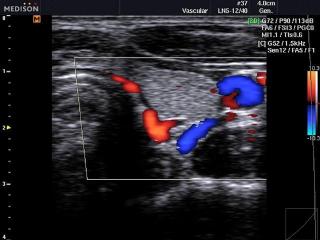

Кровоток в щитовидной железе, цветной допплер

SonoAce-R3. Кровоток в щитовидной железе, цветной допплер.